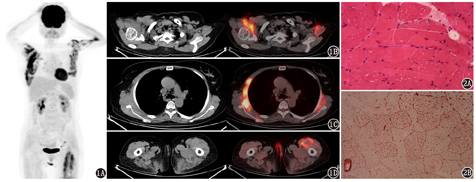

脂质沉积性肌病(LSM)患者(女,53岁)18F-脱氧葡萄糖(FDG)PET/CT显像图。最大密度投影图(1A)、平锁骨水平CT横断位及PET/CT融合图(1B)、支气管隆突水平CT横断位及PET/CT融合图(1C)、肛门水平CT横断位及PET/CT融合图(1D)示双侧肱二头肌和前锯肌、左侧股直肌边缘18F-FDG摄取明显增高,肌肉肿胀,密度稍低,肌间隙不清,肌肉及肌间隙18F-FDG摄取明显增高,大致成对称性。这种对称性头颈部、躯干部和(或)四肢近端肌肉高FDG摄取,与临床LSM患者肌损害呈对称性的特征[1]一致,LSM患者18F-FDG PET/CT影像肌肉对称性代谢活性高有一定的特征性。LSM患者也表现为头颈部和躯干肌群如咬肌、椎旁肌对称性高FDG摄取[2] 图2

同一患者左侧肱二头肌病理检查图。2A. HE染色(×200)示肌纤维大小不等,少量肌萎缩,可见部分空泡纤维;2B.油红O (ORO)染色(×200)示肌纤维脂肪明显增多,呈颗粒化